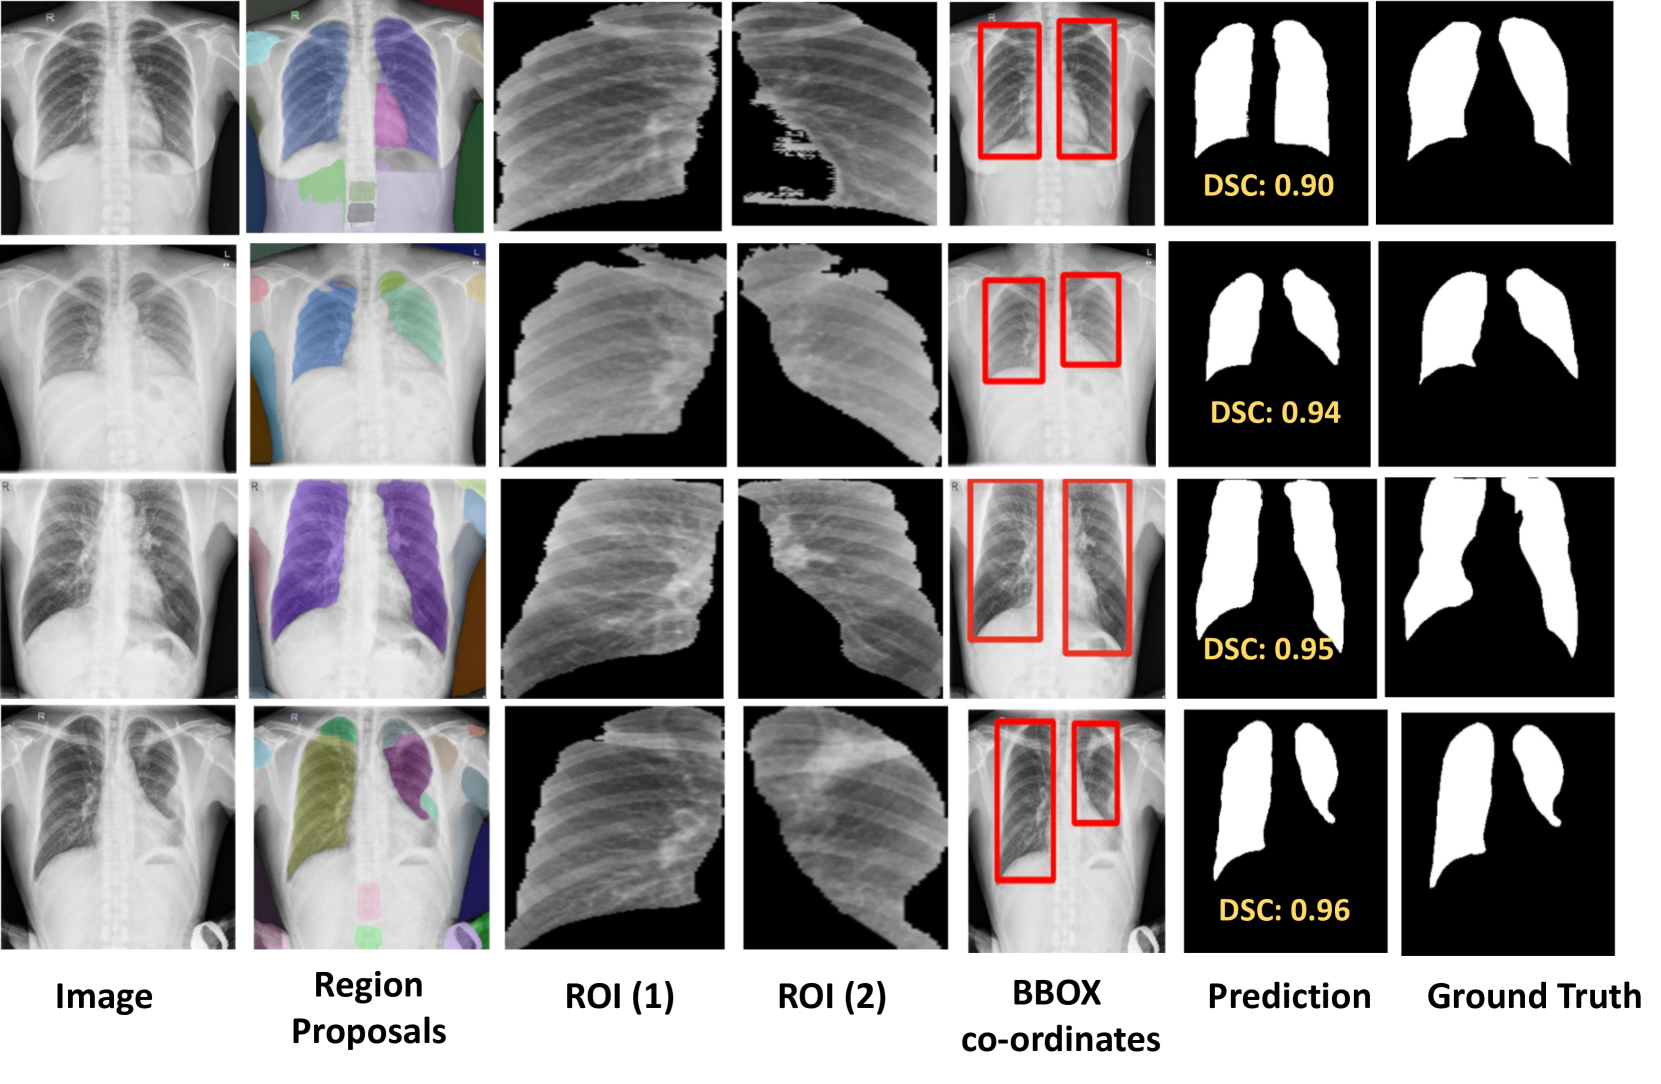

6 Qualitative Results

In this section, we comprehensively present the qualitative results of SaLIP to demonstrate its effectiveness. X-ray Masks and Labels  [19] dataset has two regions of interest i.e. left and right lungs.  Fig. 7 shows that SaLIP yields correct predictions for both lungs in a zero-shot manner without any domain expertise or prompt engineering.

Figure 7: SaLIP qualitative results on X-ray labels and masks  [19] dataset.